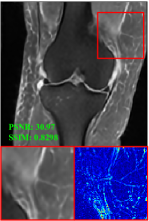

Figure 5 provides the qualitative comparison of the various methods on the four datasets at a scale of 4. The top, second, third, and bottom rows are the SR results under the FastMRI, clinical brain, clinical tumor and clinical pelvic datasets, respectively. The red boxes indicate the zoom-in region of complicated anatomical structures along with their corresponding error maps. Note that the brighter textures in the error maps, the lower the quality of the reconstructed images. As can be seen, compared to methods based on Transformers and CNNs, diffusion-based methods like DisC-Diff and DiffMSR (Ours) are capable of reconstructing high-realistic images with promising reconstruction metric scores (PSNR and SSIM). Nevertheless, while DisC-Diff can reconstruct high-precision MR images, it does not preserve the structure present in the original HR images, introducing some additional information that can affect medical diagnosis. In contrast, our method combines DM and PLWformer, which can preserve the original image’s structure while restoring high-frequency information.

In this section, we present more visual qualitative comparisons. Figures 8, 9, 10, and 11 show the reconstruction results of each method in FastMRI, clinical brain, clinical tumor, and clinical pelvic, respectively. As can be seen, although DisC-Diff can reconstruct MR images with high-frequency information, it fails to preserve the structure and content of the original Target HR image effectively, resulting in image distortion. In contrast, our proposed DiffMSR can restore high-frequency information while preserving the structure of the original HR image, indicating the effectiveness of the joint use of DM and PLWformer.